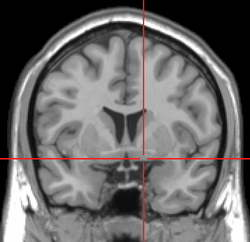

![]() Intermediate magnification micrograph of the nucleus basalis (of Meynert). LFB-HE stain. | |

NBM in relation to the globus pallidus and putamen - very low magnification.